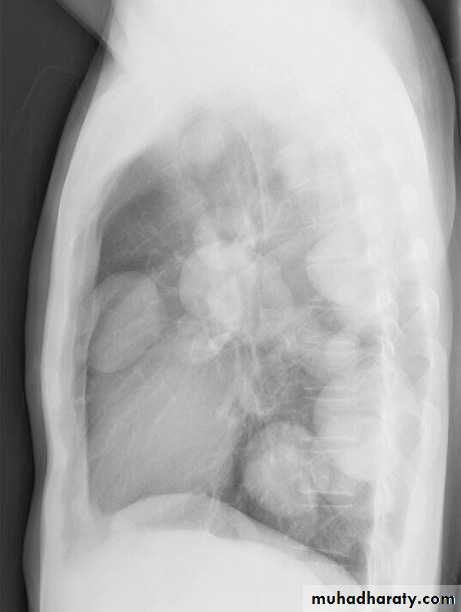

Cannon ball secondaries